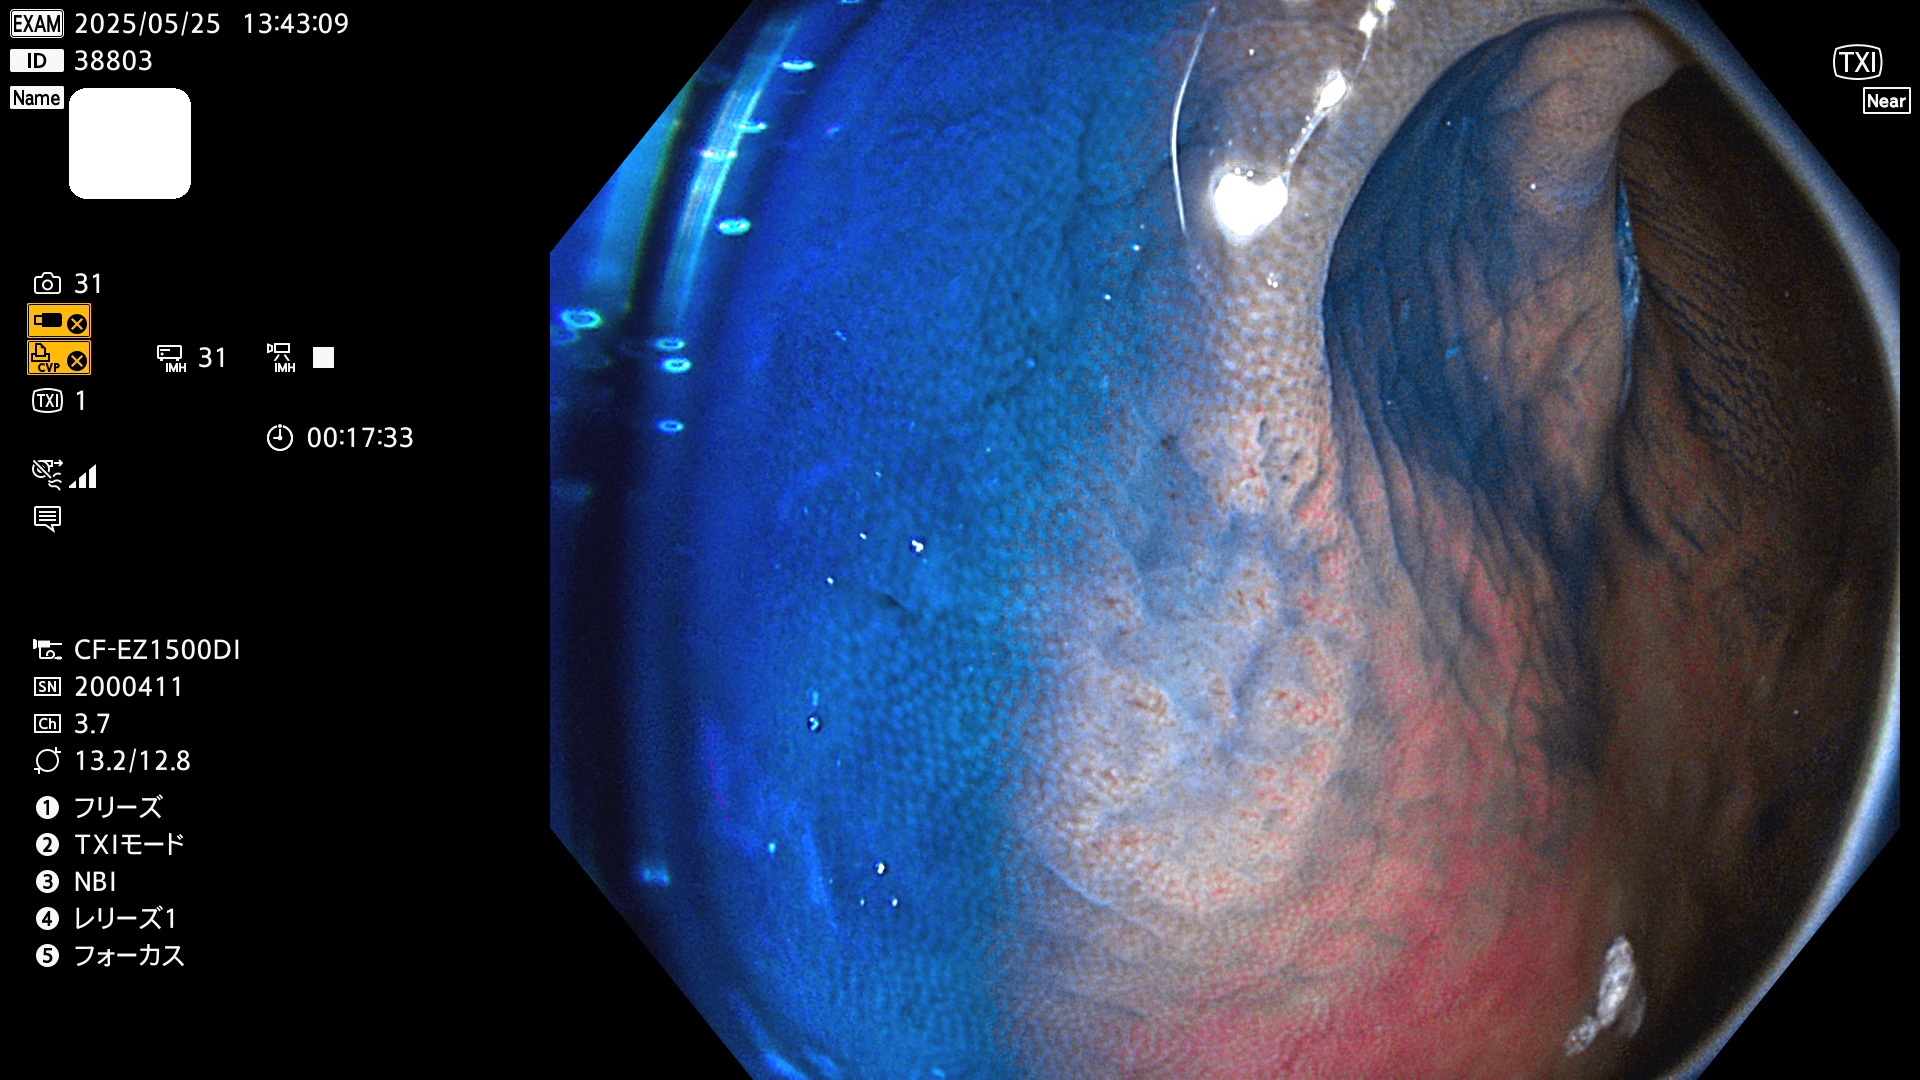

今週のUb、Uc型腺腫

完全に平坦な物をUb、陥凹している物をUcと呼びます。Ubは認識が困難で、Ucはびらん(炎症)と紛らわしいために見落とされやすく、「内視鏡後・大腸癌」の原因になります。

毎週の検査(木・金・土・日)に発見されたUb、Uc型・腺腫を、その週の日曜の夜にUPし1週間、提示します。

抽出の対象期間 2025年5月22日〜5月25日の4日間(48件の検査)10個 (10/48=21%)